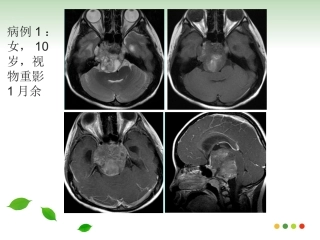

病例1:女,10岁,视物重影1月余病例2:男,47岁,视物重影2年余病例一病例二斜坡脊索瘤的影像诊断斜坡脊索瘤的影像诊断福建医科大学附属第...